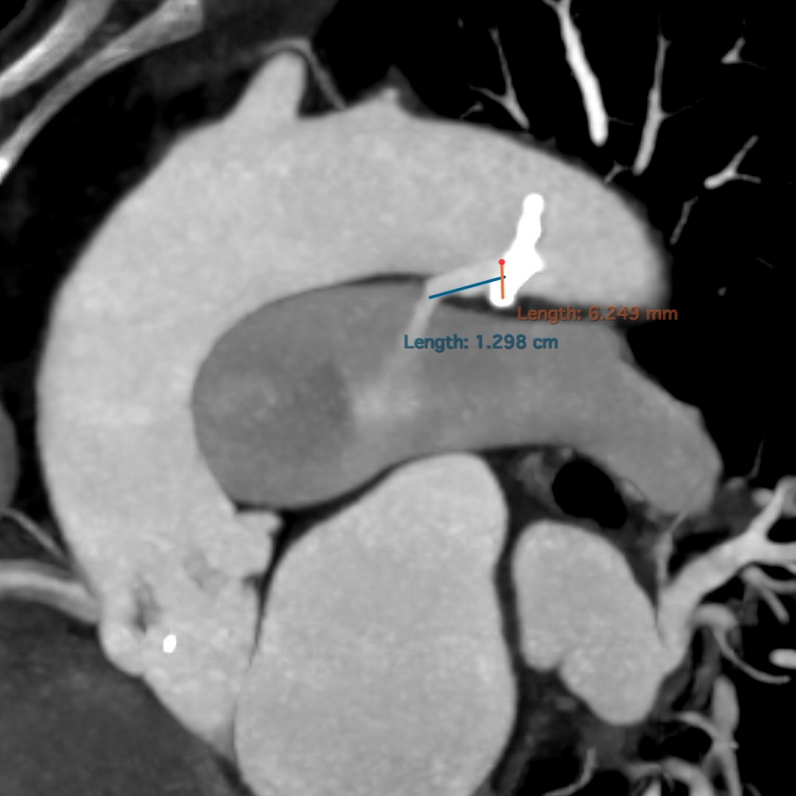

• CT显示分布的四叶瓣,瓣窦较小,冠脉开口较低,瓣叶冗长增厚,左右冠瓣叶长度均超过STJ高度。

• CT术前预估冠脉遮挡风险较高,术者团队计划Downsize选择人工瓣膜尺寸,植入21mm瓣膜,并对冠脉进行预保护,进行TAVR术治疗。

术前发现患者合并动脉导管未闭

管型6.2mmx12.9mm